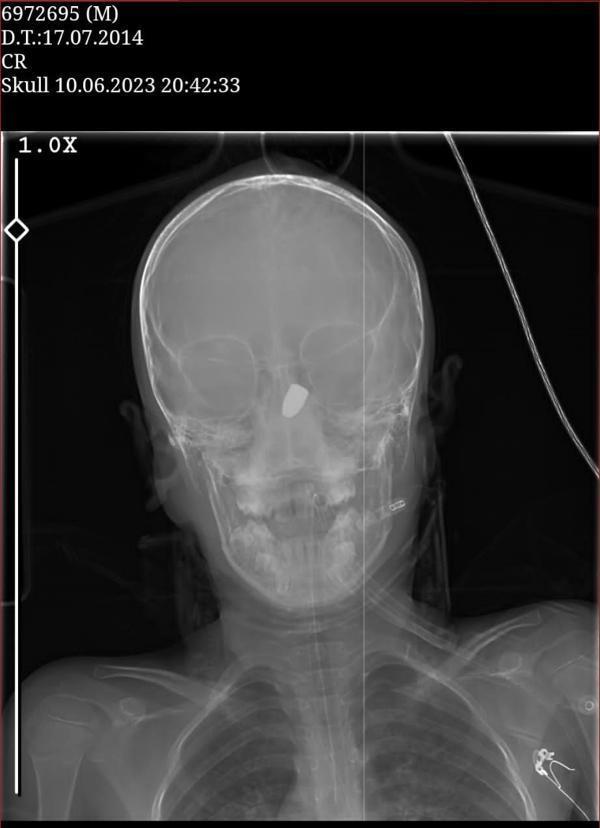

Olay, 10 Haziran'da Çukurçayır Mahallesi'nde meydana geldi. Site parkında arkadaşları ile oynayan Kerem Can Özdemir, birden kanlar içerisinde yere yığıldı. Çağrılan sağlık ekiplerince KTÜ Farabi Hastanesi'ne kaldırılan Özdemir'in çekilen tomografisinde başına yorgun mermi isabet ettiği tespit edildi. Olay ile ilgili başlatılan soruşturma sürerken, küçük çocuğun yere yığıldığı anlar da sitenin güvenlik kamerasına yansıdı. Silahı ateşleyenin belirlenmesi için İl Emniyet Müdürlüğü bünyesinde özel ekip oluşturuldu. Bölgede birçok güvenlik kamerasını mercek altına alan ekipler, şüphelinin izini sürüyor.

Yoğun bakım servisinde tedavisi süren Kerem Can Özdemir’in, risk oluşturduğu için ameliyata alınmadığı belirtildi. Beyninin 6 santimetre derinine saplanan mermi çekirdeğiyle yaşam savaşı veren Kerem Can’ın 37 haftalık hamile annesi Fatma Özdemir, olaydan 2 gün sonra aynı hastanede erken doğum yaptı. Prematüre doğup, kuvözde tutulan bebeklerini kucaklarına almayı bekleyen aile, aynı hastanenin koridorunda bir yandan da yaralı çocuklarından gelecek iyi haberi bekliyor. Özdemir ailesi hem sevinci hem de hüznü bir arada yaşıyor.